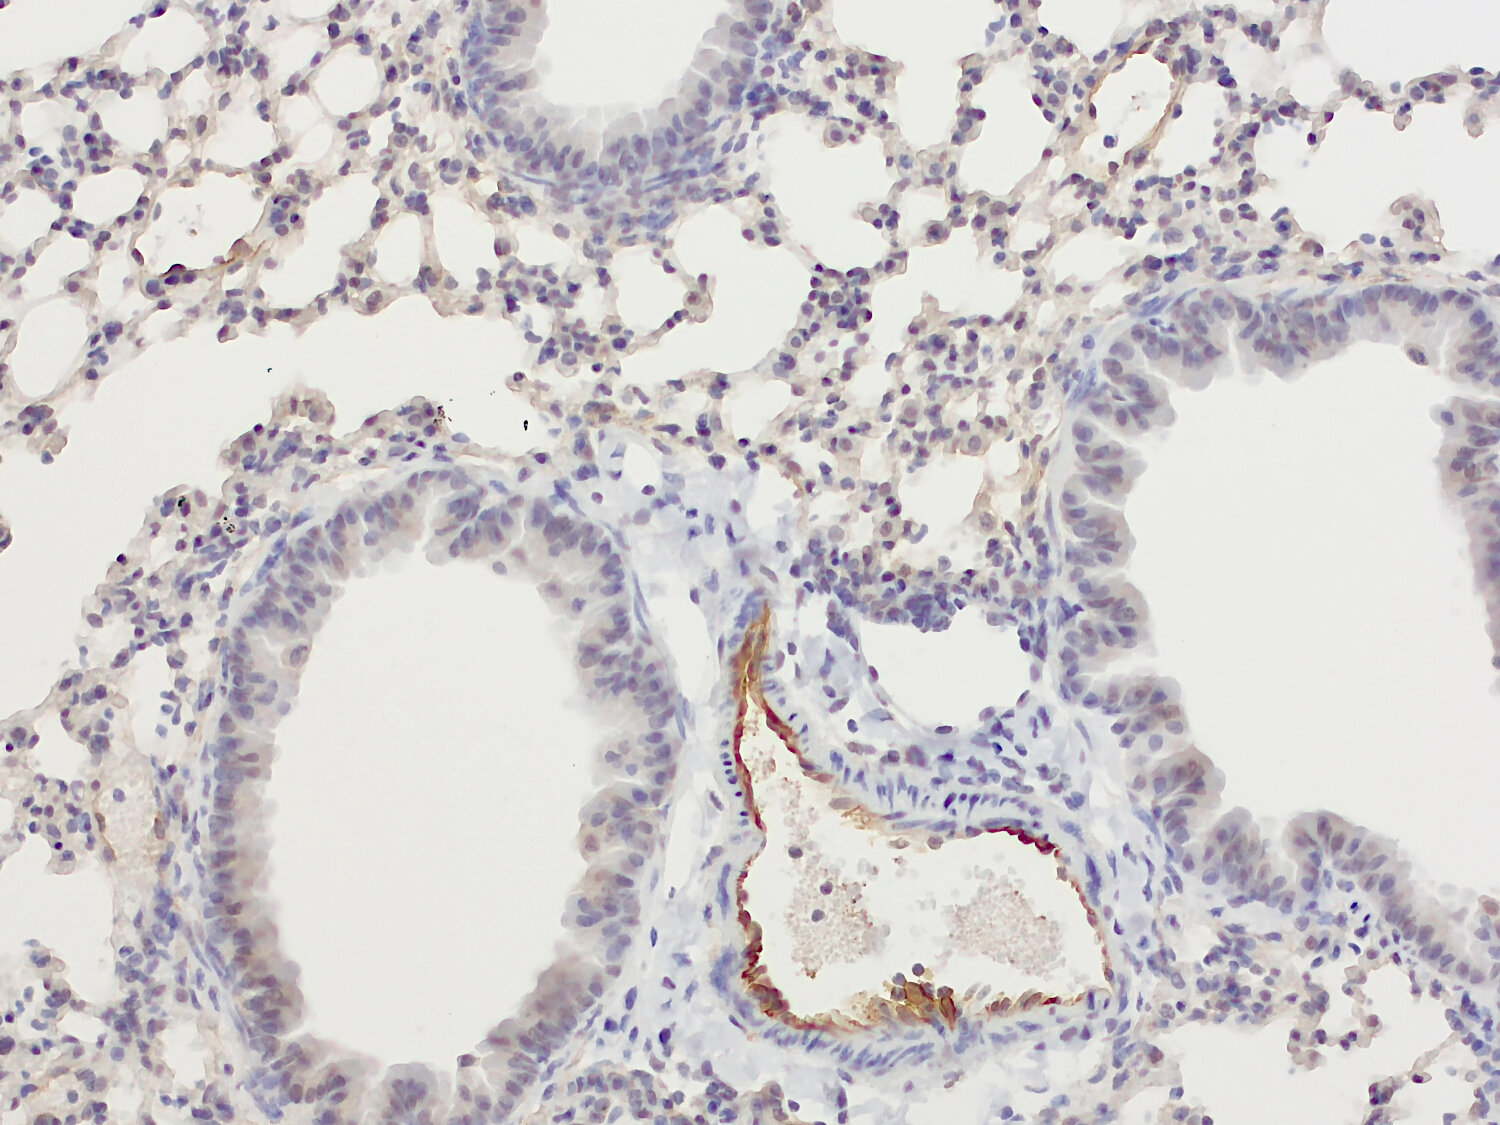

IHC-P: 1 : 1000 up to 1 : 2000 gallery

Immunohistochemistry (IHC-P) of formalin fixed, paraffin embedded (FFPE) tissue (some antibodies require special antigen retrieval steps, please refer to the ”Remarks” section). Immunoreactivity is usually revealed by fluorescence or a chromogenic substrate.

IHC: Antigen retrieval with citrate buffer pH 6 is required.

Vascular cell adhesion molecule 1 (VCAM1 or CD106) is an endothelial adhesion molecule of the Ig gene superfamily, that regulates leukocyte migration from the blood into tissues (1). Expression of VCAM1 is induced on endothelial cells during inflammatory diseases in response to a number of inflammatory stimuli, including TNFα, lipopolysaccharide or high levels of reactive oxygen species (2). VCAM1 expression in hematopoietic cells is restricted to cells confined to tissues e.g., red pulp macrophages and follicular dendritic cells in the spleen, whereas circulating cells are virtually devoid of VCAM1 (3). VCAM1 has been found to be implicated in various immunological disorders, including rheumatoid arthritis, transplant rejection and cancer and is therefore a potential therapeutic target (4).